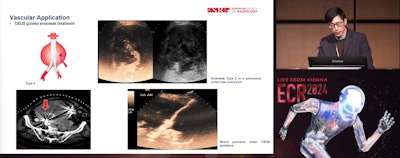

Dean Huang, MD, from King's College London highlights how contrast-enhance ultrasound (CEUS) has a wide variety of applications in diagnostic and interventional settings. Pictured, he explains how it can better visualize endoleaks.

CEUS can improve delineation of vascular lumen and can be used in peripheral vessels. It can also be used to investigate any potential bleeding or endoleaks, Huang added.

Endoleaks are a common problem in aortic vascular repair interventions. CEUS can image type 4 endoleaks and lead to more confident diagnoses, Huang added. This includes imaging the dissolving of endoleaks.